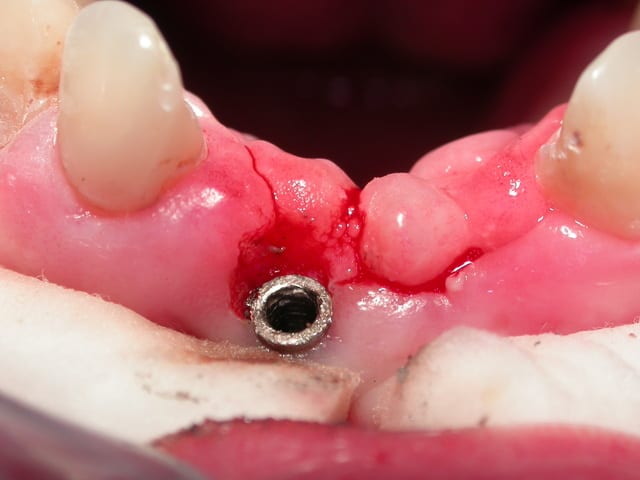

J'ai besoin d'un coup de main pour reconnaitre un implant qui a été posé sur un de mes patients (originaire de république tchèque).

Pour la partie "prothétique" bizarre je vous laisse commenté les photos.

Donc si quelqu'un reconnait le type d'implant et la marque à l'aide de la radio je l'en remercie.